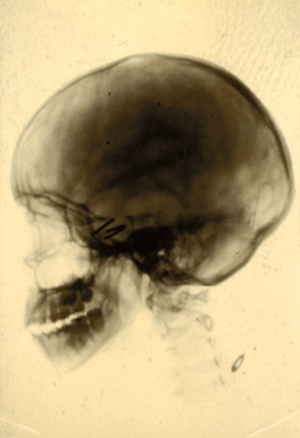

The patient apparently remained well until late June 1928 when her headaches returned and recurrence of the tumour was therefore suspected. Accordingly, in October 1928 radium needles were inserted trans-nasally into the pituitary fossa, see Figure 5 and note the substantially enlarged pituitary fossa on the x-ray.

Figure 5: Skull x-ray from 1928 showing radium needles in the enlarged pituitary fossa.